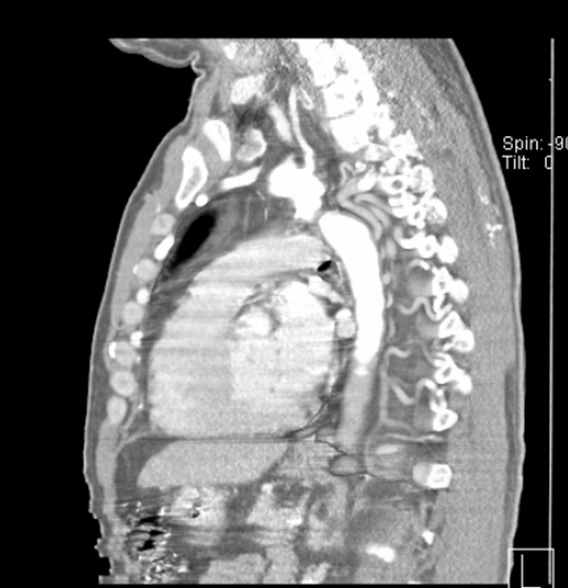

Femoral access cardiac catheterization showed complete occlusion of the thoracic descendent aorta distal to the left subclavian artery, without passage of the wire through the occlusion zone and with an 85 mm Hg gradient (Fig. 1A and 1B). Radial access cardiac catheterization showed significant proximal stenosis of the left anterior descending artery, circumflex artery, and right coronary artery.

Figure 1A and 1B: Thoracic aortogram. Aortic occlusion is evident.